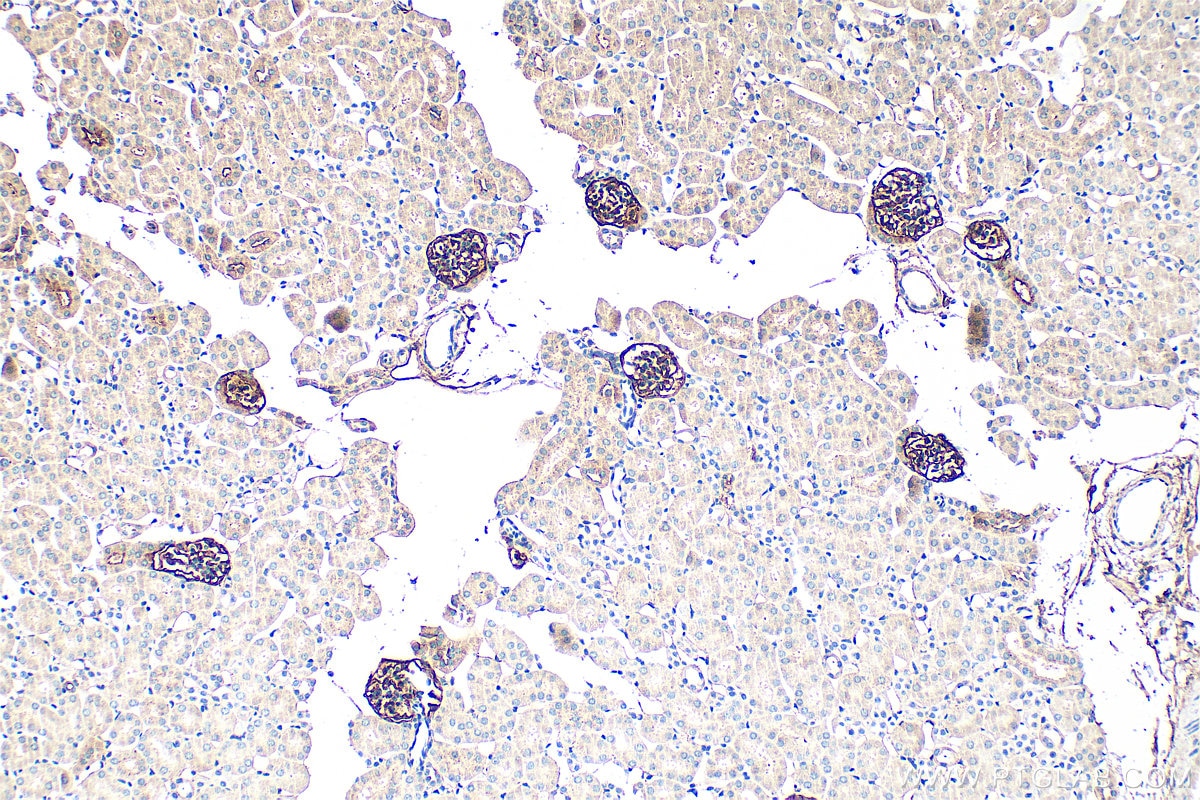

| Positive IHC detected in | mouse lung tissue, mouse kidney tissue Note: suggested antigen retrieval with TE buffer pH 9.0; (*) Alternatively, antigen retrieval may be performed with citrate buffer pH 6.0 |

33099-1-AP targets Podoplanin in WB, IHC, ELISA applications and shows reactivity with mouse samples.

Podoplanin was identified as a glycoprotein found in the cell membranes of glomerular epithelial cells (podocyte) (PMID: 9327748). It is a lymphatic marker because the expression of podoplanin has been detected in lymphatic but not blood vascular endothelium, and is useful as the marker of tumor-associated Lymphangiogenesis. Podoplanin has a function in developing testis, most likely at the level of cell-cell interactions among pre-meiotic germ cells and immature Sertoli cells. It may be involved in cell migration and/or actin cytoskeleton organization. When expressed in keratinocytes, PDPN induces changes in cell morphology with transfected cells showing an elongated shape, numerous membrane protrusions, major reorganization of the actin cytoskeleton, increased motility and decreased cell adhesion. It is required for normal lung cell proliferation and alveolus formation at birth. PDPN induces platelet aggregation. It does not have any effect on folic acid or amino acid transport and does not function as a water channel or as a regulator of aquaporin-type water channels.